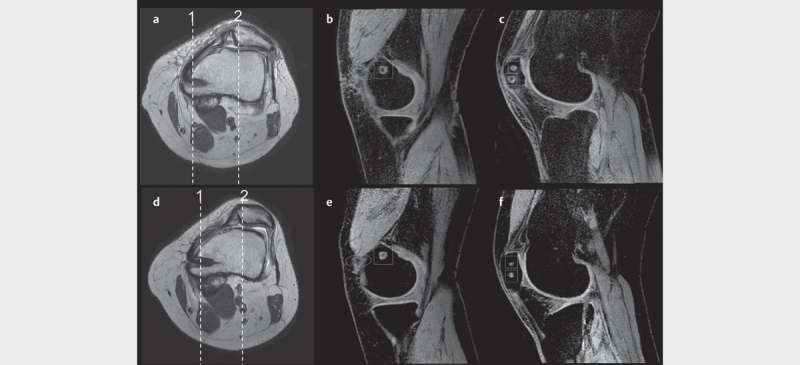

The resumption of blood flow is an important factor in the remodeling process of the graft. The purpose of this study is to evaluate hemodynamic changes after medial patellofemoral ligament (MPFL) reconstruction using magnetic resonance angiography (MRA) as the evaluation of graft remodeling. Eleven knees that underwent anatomical MPFL reconstruction with the semitendinosus tendon were studied. We evaluated the blood flow around the bone tunnel wall in the arterial phase using MRA approximate 3 months and 1 year after surgery. Clinical and radiological evaluations were also analyzed. MRA showed an inflow vessel into the bone tunnel wall from the medial superior genicular artery on the femoral side, and from the articular branch of the descending genicular artery and the medial superior genicular artery on the patellar side. This contrast effect was decreased at 12 months after surgery in all cases. The clinical scores improved from baseline one year postoperatively. We revealed the blood flow to the bone tunnel wall after anatomical MPFL reconstruction is detected by MRA. The blood flow started within 2 or 3 months postoperatively and was sustained for 12 months. This study supported remodeling of the graft continues 3 months after surgery when the conformity of the patellofemoral joint stabilizes.